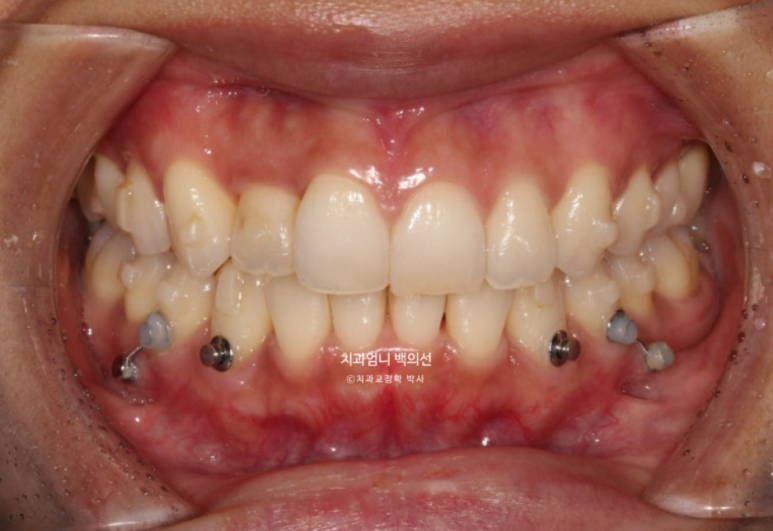

멀리서 오시기에 내원간격 때문에 인비절라인 치료를 선택하셨고 23년 10월부터 24년 8월까지 첫세트 44개 장치를 모두 낀 후 모습입니다

중심선은 잘 맞으나 입천장에 위치했던 축절치가 아직 완벽하게 제자리를 찾지 못했습니다.

덧니의 머리부분은 앞으로 잘 나와 있지만

교합면에서 보면 입천장에 위치했던 덧니 뿌리 부분은 아직 입천장 쪽에 위치해 있습니다.

여담으로 앞니 반대교합이 해소되는 과정에서는 대합치와 엉킨부분이 풀리는 과정에서 서로 먼저 닿는 조기첩촉 시기가 있습니다.

중간 과정상 불가피한 부분이지만 이 시기에는 먼저 닿아 어금니가 잘 안 닿고 해당치아끼리 자주 부딪쳐 불편합니다.

아래치열은 더 이상 고칠 것이 없어보입니다.

스마일 사진을 찍어 중심선 체크도 합니다

덧니쪽으로 쏠려있던 중심선은 이제 중앙을 찾았습니다.